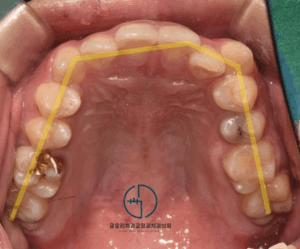

망우동 치과 정중선 편위 및 삐뚤어진 치열, 가지런한 배열을 회복하기 위한 발치 교정

안녕하세요 망우동 치과 김정은 원장입니다. 치아가 삐뚤어 교정 상담을 받게 되면 많은 분들이먼저 궁금해하시는 것이 바로 비발치 인지 발치 교정인지에 대한 부분입니다. 23.07.18 가능하다면 치아를 뽑지않고 배열만 정리하는 비발치 방식을…